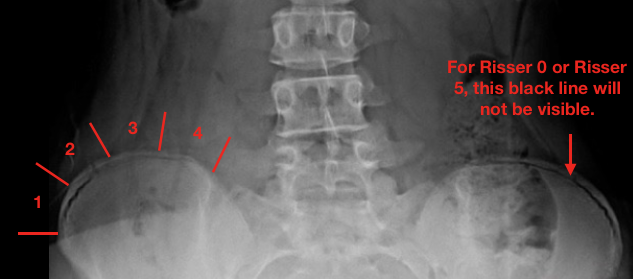

방사선에서도 쉽게 관측할 수 있는 것이 바로 장골골단 입니다.

장골 골단의 골화는 Anterior Superior Iliac Spine 에서 시작하여 Posterior Superior Iliac Spine 까지 진행하게 됩니다. 골골화가 4단계 까지 진행된 후에 완전히 골화가 진행되어 5단계가 되게 됩니다.

각 단계마다 확인해보면 1단계는 25% 이하, 2단계는 25~50%, 3단계는 50~75%, 4단계는 75~100% 골화가 진행되는 것으로 분류하고, 5단계는 장골에 유합되는 것입니다.

아래는 Risser 4 사진임을 유추해 볼 수 있습니다. 척추의 성장이 거의 끝난 상태인 것이지요.